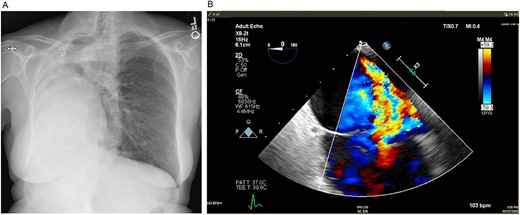

Mild–moderate TR was first noted on transthoracic echocardiogram 5 years after pneumonectomy and continually worsened over the next 10 years until she had wide open severe TR with moderate RV dilation and moderate global reduction in RV function. After multidisciplinary evaluation, TVR was recommended. Preoperative imaging revealed notable mediastinal shift to the right, severe counterclockwise rotation and displacement of the heart to the right and expansion of the left lung into the right hemithorax (Figs 1 and 2).

(A) Preoperative posteroanterior view chest X-ray showing left to right mediastinal contents shifted and a clear left lung. (B) Preoperative transesophageal echocardiogram with doppler showing severe tricuspid regurgitation with no coaptation between the anterior and septal leaflets.